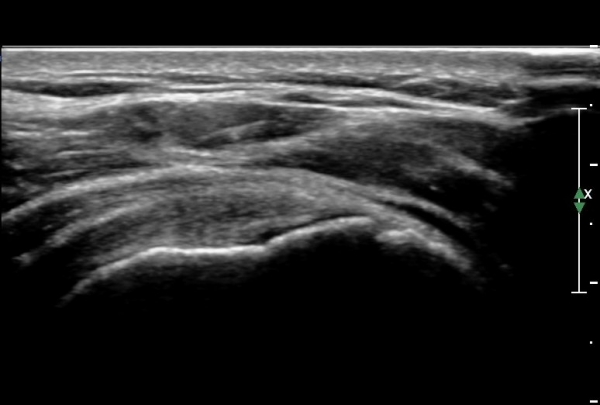

°ßºÀÈ¸Ãø Ãæµ¹ÁõÈıº°Ë»ç(°íÂû »çÁø Âü°í)¿¡¼­ °ßºÀ¿ÜÃø¿¡ ¼ö¾×ÀÌ Àú·ùµÇ°í °Ë»ç ½Ã

°ßºÀ ¾Æ·¡¿¡¼­ ÀâÀ½(crepitus)ÀÌ ´À²¸Áü.(»çÁø 6).